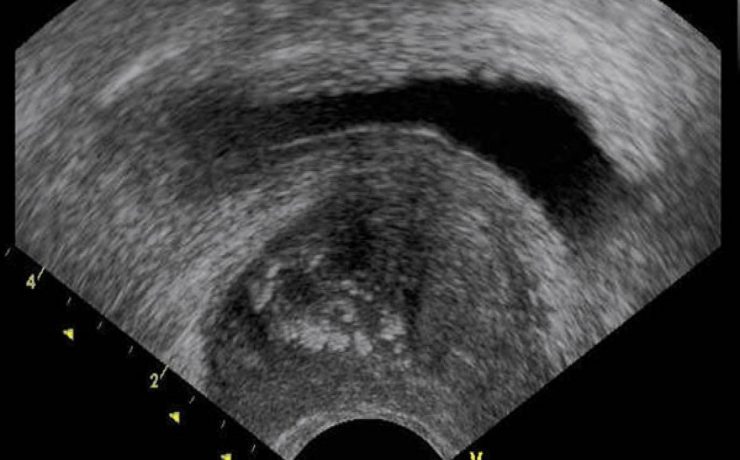

Rotura uterina por acretismo placentario

La rotura uterina durante el embarazo es una de las complicaciones más graves, que aumenta la morbilidad y mortalidad materna y fetal. La rotura uterina por placenta percreta es rara. La rotura uterina es cualquier desgarro, fracción o solución de continuidad supracervical en el útero que sucede durante el embarazo,